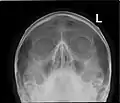

Paranasal sinuses seen in a frontal view

Paranasal sinuses are a group of four paired air-filled spaces that surround the nasal cavity.[1] The maxillary sinuses are located under the eyes; the frontal sinuses are above the eyes; the ethmoidal sinuses are between the eyes and the sphenoidal sinuses are behind the eyes. The sinuses are named for the facial bones and sphenoid bone in which they are located. Their role is disputed and no function has been confirmed.